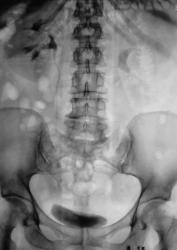

Пол пациента: Мужской пол Тип патологии: Другое Область исследования: Мочеполовая система Методы исследования: Rg Пациент направлен в рентгеновский кабинет для производства внутривенной урографии с подозрением на опухоль левой почки. Произведено стандартное исследование. Ваше мнение коллеги? Вс, 24/05/2009 - 21:05 #1 Андрей Юрьевич Не на сайте Был на сайте: 1 неделя 4 дня назад Зарегистрирован: 16.11.2008 - 22:16 Публикации: 18098 Такой можно и коралловидным назвать. Андрей Юрьевич Пнд, 25/05/2009 - 10:47 #2 v1tal Не на сайте Был на сайте: 4 года 9 месяцев назад Зарегистрирован: 07.06.2008 - 19:41 Публикации: 1779 А сколько лет пациенту? В анамнезе туберкулеза нет? "Знаешь, у некоторых врачей есть комплекс мессии — им необходимо спасать мир. А у тебя комплекс Рубика — тебе необходимо решать головоломки." Пнд, 25/05/2009 - 15:45 #3 Катенёв Валенти... Не на сайте Был на сайте: 7 лет 3 недели назад Зарегистрирован: 22.03.2008 - 22:15 Публикации: 54876 В анамнезе туберкулёза (легочного) нет. Пациенту 42 года. Мочу, сейчас, у всех пациентов с "урологической патологией" на МБТ и "смотрят и сеют". А какое мнение коллег по поводу правой почки?

Такой можно и коралловидным назвать.

В анамнезе туберкулёза (легочного) нет. Пациенту 42 года. Мочу, сейчас, у всех пациентов с "урологической патологией" на МБТ и "смотрят и сеют".

А какое мнение коллег по поводу правой почки?